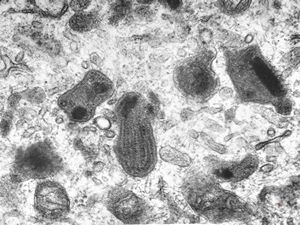

rat | skeletal muscle 6h. post ex. … changes of mitochondrial cristae